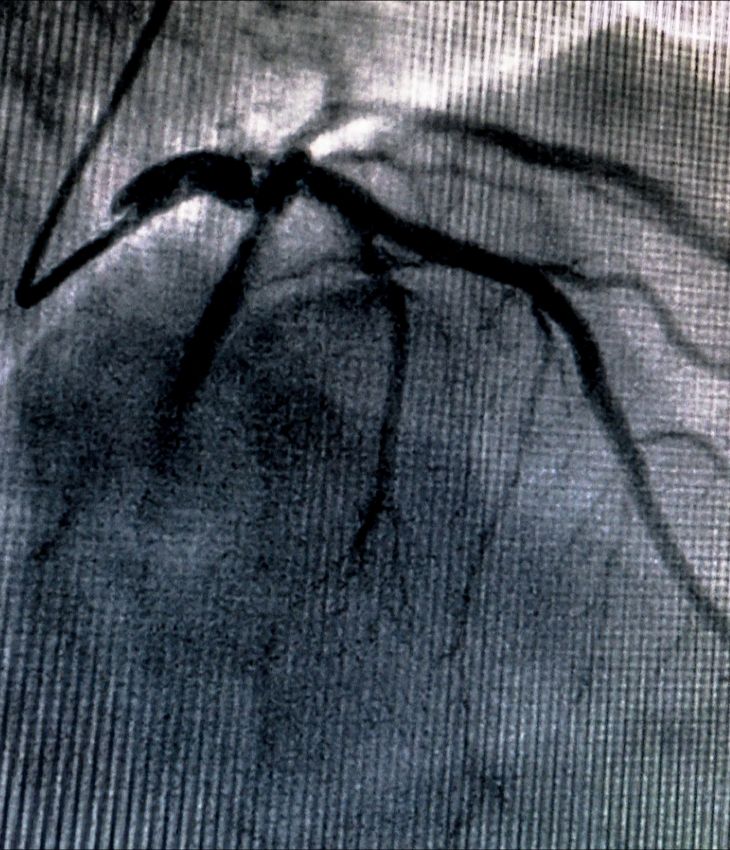

- Suspected coronary artery disease: To detect narrowed or blocked arteries non-invasively using CT coronary angiography.

Depending on your results, he may recommend further investigations, medical therapy, or interventional procedures. These tests are safe, accurate and non-invasive, though CT scans involve minimal radiation. With private clinics in London you’ll receive clear answers and a proactive care plan tailored to your cardiac health.